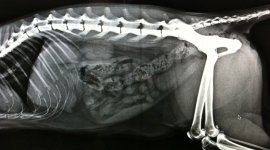

Radiologia digitale

La radiologia medica è la branca della medicina che si occupa della produzione e dell'interpretazione a fini diagnostici o terapeutici di immagini radiografiche. La tecnologia digitale consente di sottoporre a studio in modo dettagliato, approfondito e rapido le immagini radiografiche ottenute. La radiologia consente ai medici di valutare:

- patologie a carico dei polmoni e dell’apparato respiratorio

- patologie osteoarticolari, incluse le malattie genetiche giovanili (per es. per la displasia dell’anca e del gomito)

- patologie cardiovascolari

- patologie dell’apparato gastroenterico, anche utilizzando il mezzo di contrasto

- patologie del tratto genito-urinario

- patologie ostetriche-ginecologiche e monitoraggio dell’ultimo periodo della gravidanza